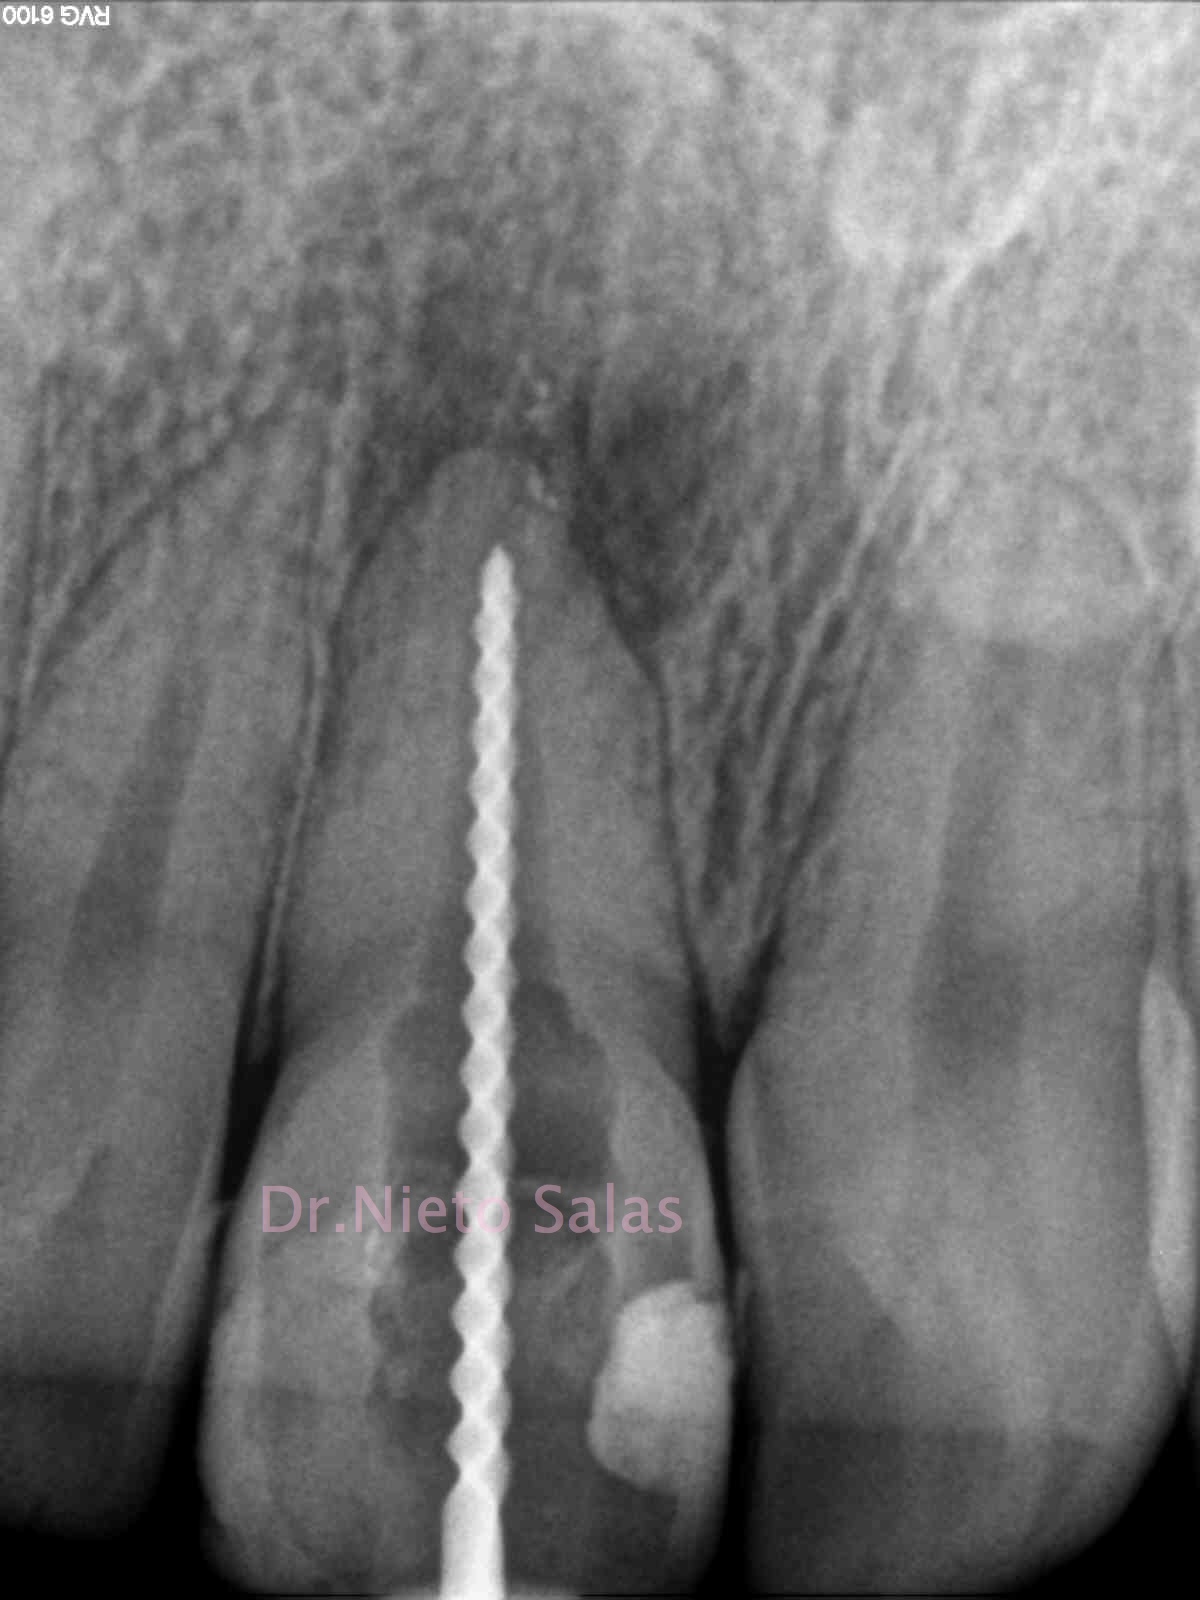

El primer caso, se trata de una pieza que nos mandan, un 1.2, con una apertura, para ver que podemos hacer:

Como podemos apreciar, se trata de una pieza con una reabsorción externa en el tercio apical e incluso del mismo ápice, y en el cuello se observa un defecto. Desde un primer momento, se le explica al paciente que el pronóstico del mismo es dudoso y que puede que necesite complementar el tratamiento con una microcirugía apical.

Le planteamos el tratamiento con un sellado apical con M.T.A. por si necesitásemos hacer la cirugía endodóntica, y posterior sellado con gutapercha termoplástica.

Decidimos colocar un medicamento intraconducto durante unos 15-20 días. Nuestro medicamento de elección será el Hidróxido de Calcio, sabemos que tiene una influencia sobre los osteoclastos , reduciendo su actividad, y estimulando la reparación (Tronstad 1981). El uso del M.T.A. también tiene un componente de acción muy similar al Ca(OH)2, con lo que también nos ayudará.

(Orto) (Disto)

Como hemos comentado anteriormente, crearemos una barrera apical con M.T.A., asegurandonos el sellado del mismo. Y finalmente sellaremos con gutapercha termoplástica con la Pistola Obtura II.

Llamamos al paciente a revisión al año:

Vemos una regeneración de la lesión, con lo que va evolucionando positivamente. El defecto en el cuello del diente, sigue presente, se planificó el caso para realizarlo en el momento de la cirugía, pues pensábamos que al final necesitaríamos complementar el tratamiento, pero ahora solo vamos a vigilar la pieza.